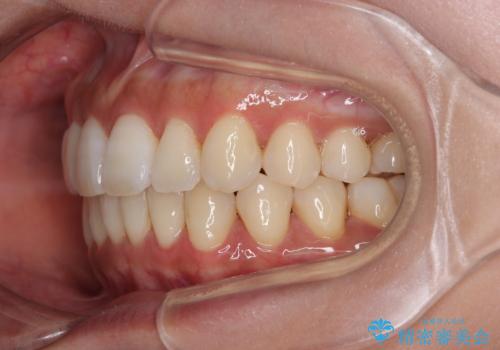

【モニター】上顎前突と奥歯の鋏状咬合 補助装置を用いたインビザライン矯正治療

- 前歯の歯列不正と奥歯の咬みにくさを気にして来院された患者様です。

インビザラインでの矯正治療を希望されていましたが、奥歯の咬み合わせがインビザライン単独では改善困難と判断されたので、補助装置を併用することとしました。

上顎最後臼歯は極端に外側を向いており、下顎骨に対して上顎骨が前方に位置していたため、補助装置により最後臼歯を一気に内側に引き込むとともに、上顎臼歯を後方移動させ、奥歯の咬み合わせが改善した後に、上下インビザラインにより歯列全体を整えていくこととしました。

奥歯の咬み合わせを事前に望ましい位置に改善したことで、インビザライン単独では改善が最も困難な状況を排除することができ、非常に理想的な仕上がりとなりました。